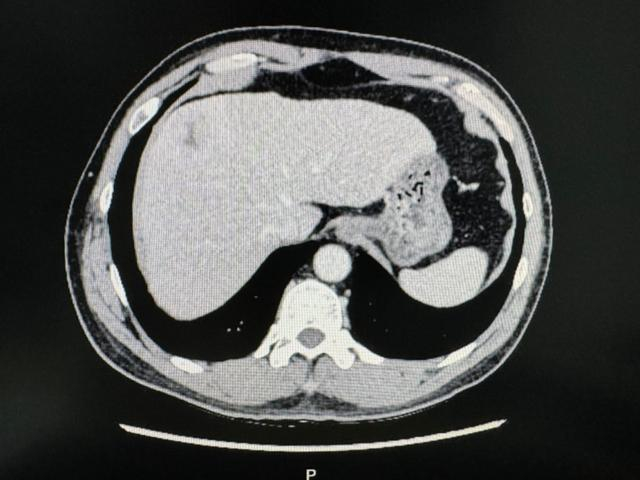

在住院期间,患者查上腹部CT后提示肝左右叶交界处肝癌,经同济医院肝胆外科中心主任谭蔚锋会诊后进行后续治疗。

术前影像学资料

1月4日行腹腔镜下特殊肝段切除术(肝中叶IVA+VIII段),术中病理为肝细胞癌。